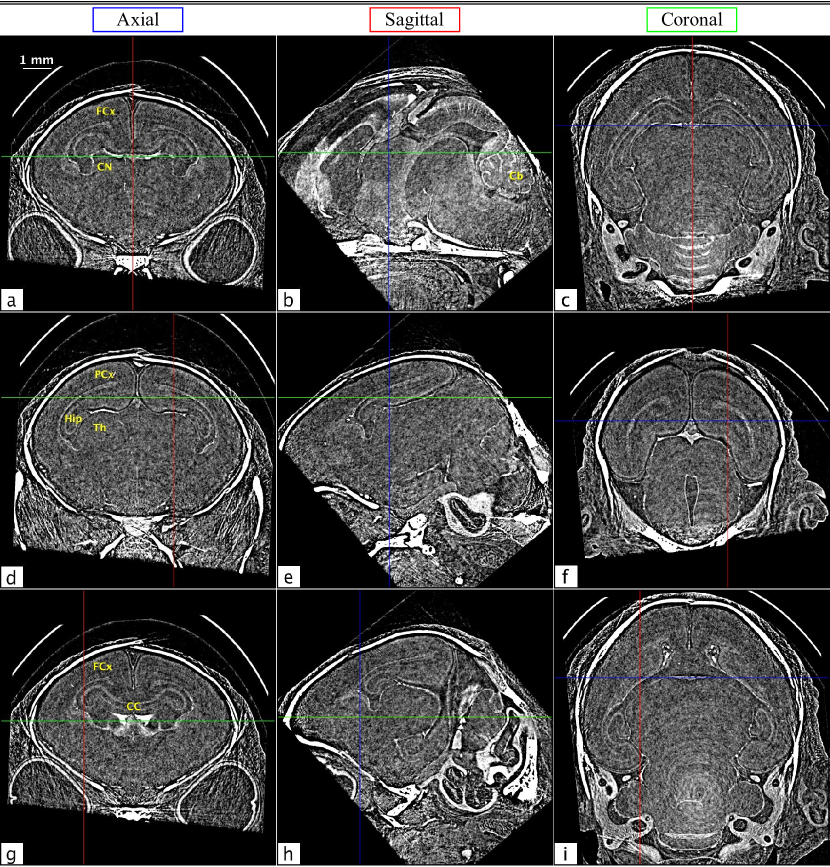

Rabbit kitten brain CT

The full volume of the in situ rabbit kitten data set was reconstructed using filtered back projection (FBP) and rotated to create axial, sagittal, and coronal views for both absorption contrast and phase retrieved PBI CT (Δδ/Δμ=5.66×1010Δ𝛿Δ𝜇5.66superscript1010\Delta\delta/\Delta\mu=5.66\times 10^{-10}). Several slices of the absorption contrast CT volume can be seen in Fig. 7. The views are denoted in blue, red, and green for axial, sagittal, and coronal, respectively, and the crosshairs on each panel correspond to the locations from which the other two views in that row are cut. Note that all of the images in Fig. 7 are conspicuously featureless apart from some bone. However, in the corresponding phase retrieved views in Fig. 8, grey and white matter boundaries are resolved, and several specific brain features are clearly delineated. The overall SNR gain with phase contrast brain CT was found to be 19.7±plus-or-minus\pm1.5. This was determined using six of the flattest regions in each image, where the SNR is the ratio of the mean to the standard deviation of each region. This number may seem surprisingly small, given the marked improvement between Figs. 7 and 8; however, since the radiation dose required is inversely proportional to the square of the gain[9], we can see that similar-to\sim400 times more dose would be required to obtain the same result with conventional absorption contrast CT.

Remarkably, the brain structures visible in these images are not obscured by streak or ring artefacts. This is due to the volume being rotated with respect to the CT acquisition plane in which the artefacts are created; hence the artefacts are minimised. In panel 8a, the frontal lobe, frontal cortex, and striatum can be seen. Panel 8d shows the parietal cortex, hippocampus and thalamus, and in panel 8g the frontal cortex, corpus callosum, and caudate nucleus are all clearly resolved. The strongest streak artefacts can be seen in the axial images. This is because the axial orientation corresponds to only slightly acute angles with respect to the acquisition plane, while the angles of the other orientations are much larger.

Refer to caption

Figure 7: Several axial (a, d, and g), sagittal (b, e, and h), and coronal (c, f, and i) absorption contrast tomograms from in situ brains from dead rabbit kittens. The crosshairs on each image denote the locations of the slices from the other orientations in each row, with axial, sagittal, and coronal slices marked in blue, red, and green, respectively.

Figure 8: The same slices from Fig. 7, now with phase contrast and phase retrieval. As with Fig. 7, axial, sagittal, and coronal views are marked in blue, red, and green, respectively. Circularly symmetric ring artefacts can be seen as a white blurring toward the bottom of panels 8(c) and 8(i). These also manifest as a diffuse white band in panel 8(b), running from the lower centre of the image toward the cerebellum (Cb). Note that these artefacts are not visible in the absorption contrast images in Fig. 7, since there they are below the level of the noise. Reference labels delineated in coronal sections are observed at the level of the frontal cortex (FCx) in images 8(a) and 8(g), and level of the parietal cortex (PCx) in 8(d), showing the caudate nucleus (CN), hippocampus (Hip), thalamus (Th) and corpus callosum (CC).

In general, streak artefacts pose a particular problem for brain PCXI-CT due to the very low contrast between structures within the brain. Streaks that are not distinguishable above the noise in absorption contrast CT can dominate brain structures once that noise has been suppressed on phase retrieval, since they often display similar or even higher contrast. The many possible causes of these artefacts can also be very difficult to decouple. Nevertheless, we find that by paying particular care to the orientation of the sample in the CT acquisition plane, we can minimise these effects. Some residual streak artefacts still persist, and further investigation is required to determine the most appropriate method by which to correct for these effects. For preclinical studies (e.g. tissues from deceased animals or brief terminal experiments under anaesthesia) where dose is not an issue, or for studies involving non-biological samples, it should be possible to eliminate all of these artefacts by acquiring two or three CTs in orthogonal orientations.

Ring artefacts can also be seen in the lower part of the coronal images of Fig. 8. As with the streak artefacts, these are minimised by sectioning slices at an angle with respect to the CT acquisition plane. For this volume, the coronal orientation is offset by 40 from the acquisition plane. This means that fewer consecutive image pixels contain ring artefacts originating from the same detector elements, reducing structure in the artefacts. The artefacts, however, persist to some degree along the readout direction of the detector. This results in a diffuse band that can be seen across panel 8b from the lower centre of the image, running diagonally upward and to the right, through the cerebellum. This effect is most prominent at the centre of rotation of the sample and becomes less so at larger radii.